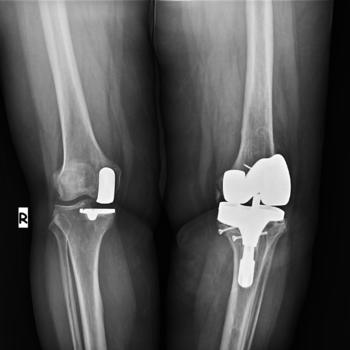

What is partial knee replacement?

Partial knee replacement, also called a unicondylar knee replacement, is a surgery that may be considered for treatment of osteoarthritis of the knee joint if the arthritis in the knee is confined to a limited area. Partial knee replacements are an alternative to Total Knee Replacement and can be recommended for patients who are:

Several studies have demonstrated the advantages of this treatment option over the more conventional Total Knee Replacement. These include: a smaller scar, less pain, a potentially shorter hospital stay, a faster rehab and recovery time, and possibly a greater range of motion when compared to standard total knee procedures. In addition, because more of the knee remains untouched, patients often report that the knee feels more normal to them.

Partial Knee replacement surgery details

The surgery takes about one and a half hours. An incision is made over the knee and the worn out cartilage is exposed. The rough edges of the end of the femur (a bone that goes from the hip to the knee) and top of the tibia (a bone that goes from the knee to the ankle) are cut flat, cleaned, and then the unicompartmental device is cemented in place. The devices used at our partner hospitals are western brand ones such as Biomet Oxford II.